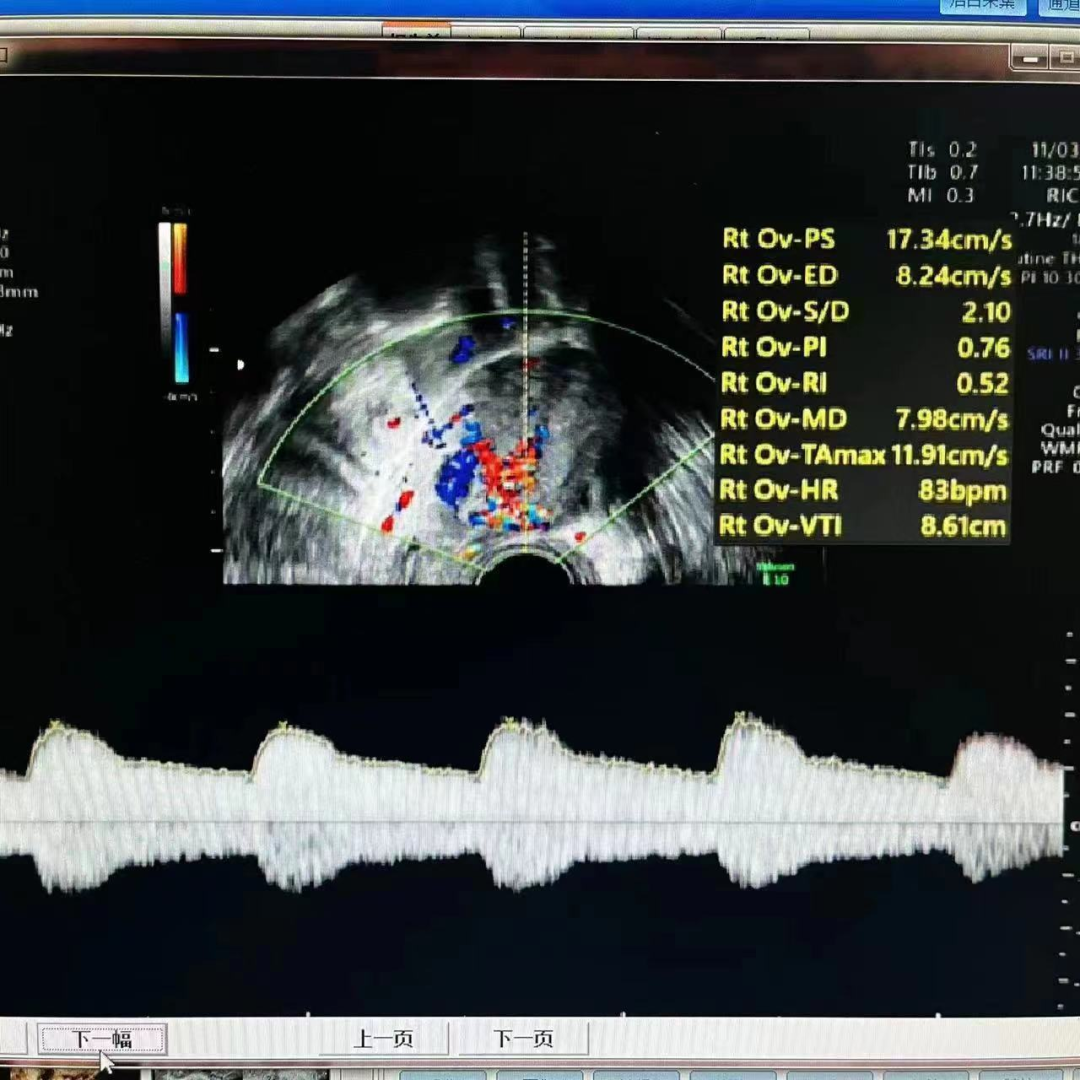

编者按 剖宫产瘢痕妊娠,是指受精卵在子宫切口上着床,在临床上这种情况要引起高度的重视,会随着妊娠囊的增大,造成局部的破裂,后果非常严重。本期【病例分析室】由山西省人民医院主任医师王素琴为大家分享一例剖宫产瘢痕部位妊娠(药流后)合并动静脉瘘,对于此情形,她是如何进行诊断和治疗的,详见以下病例分析。 病例介绍 患者29岁,主因“药流后2月,发现瘢痕妊娠4天”入院。 现病史:停经40天于当地医院行药流术,术后20天盆腔彩超未见异常。术后2月因“月经未复潮”就诊于我院,行盆腔彩超提示:瘢痕妊娠III型,动静脉瘘不除外。考虑“瘢痕妊娠”入住我科。血HCG:229.56mIu/mL。追问病史:药流术后未同房。 既往史:2009年、2021年于当地医院行剖宫产术。 婚育史:G4P2。 月经史:平素月经规律,5/25天,LMP:2022-07-01。 妇科检查:外阴正常,已婚未产型;阴道通畅,可见少许分泌物;宫颈光滑,前穹隆呈紫蓝色,触血阴性;宫体前位,大小约7*6cm大小,表面光滑,活动好,无压痛;双附件区未见明显异常。 辅助检查: 1)盆腔彩超: 子宫前壁下段瘢痕处可见44.4*34.3mm混合回声包块,向膀胱隆起,包块与膀胱间肌层变薄,厚约0.7mm,CDFI:包块内部及周边可见极丰富血流信号,可探及动静脉血流谱。考虑子宫前壁下段瘢痕处混合回声包块(瘢痕妊娠III型,动静脉瘘不除外)。 2)盆腔核磁: 子宫前壁下段瘢痕处及宫腔内见团块状异常信号影;病变周缘伴粗大迂曲血管。 3)血HCG:229.56mIu/mL。 术前诊断:剖宫产部位瘢痕妊娠III型(药流后)动静脉瘘?